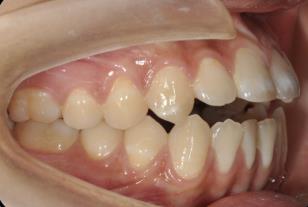

3. 前牙深覆合深覆盖

前牙深覆合是指上前牙覆盖下前牙唇面超过1/3,深覆盖是指上前牙的唇面与下前牙唇面之间的水平距离超过3mm,常常伴有下颌后缩,侧貌呈现凸面型。

矫治方法:前牙深覆合深覆盖的患儿常常伴有吮指,咬下唇,口呼吸等不良习惯,同样,应首先纠正其不良习惯,必要时可在其手指上涂抹苦瓜汁或是辅助矫治装置如唇挡丝、前庭盾等。同时早期可进行肌功能训练,如上唇肌张力训练。口呼吸习惯应进行耳鼻喉科会诊处理,检查其是否伴有鼻咽部疾病,排除鼻咽部疾病后,再使用前庭盾、闭口贴等纠正。针对功能性的因素,常用的矫治器为肌激动器,TB、FRⅡ。针对骨性的因素,常用的矫治器为头帽-肌激动器。